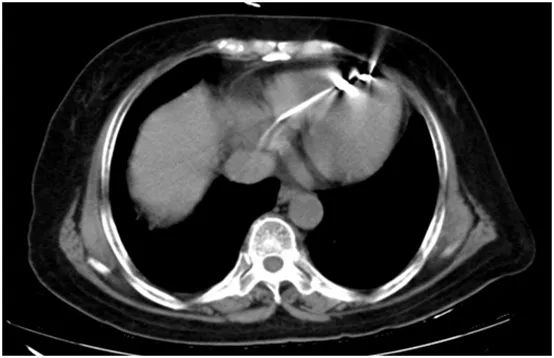

图3. 患者的胸部CT检查证实起搏电极位于右室心尖。